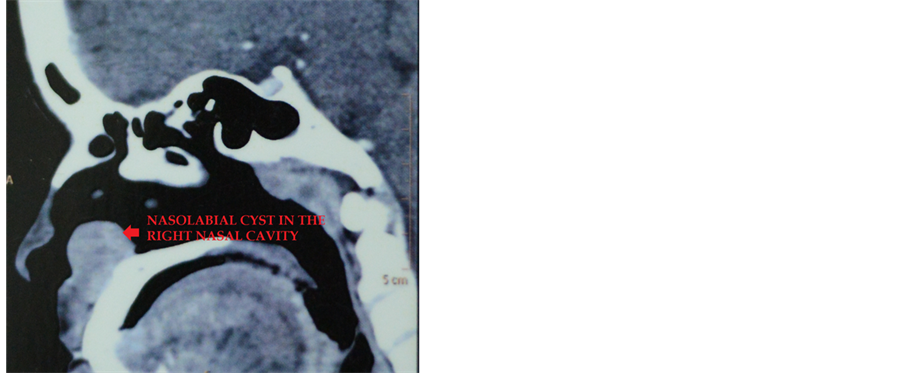

A CT (computed tomography) with contrast of the paranasal sinuses revealed a 2.3 × 2.1 cm round mass like lesion in the right anteroinferior nasal cavity. CT attenuation value measured 59 HU on plain scan and 73 HU on post contrast study, with homogenous enhancement. There was minimal scalloping of the adjacent maxillary bone but no obvious erosion (Figure 2).

Figure 2. CT scan showing the nasolabial cyst in the right nasal cavity (axial and sagittal cuts respectively).

CT scan can help to exclude mass lesions causing bony erosion and most of the differentials. Though in the literature, rare cases of radicular absorption due to these cysts do exist. However, minimal scalloping of the maxillary bone as observed in our case was also observed by other authors [13] [14] .